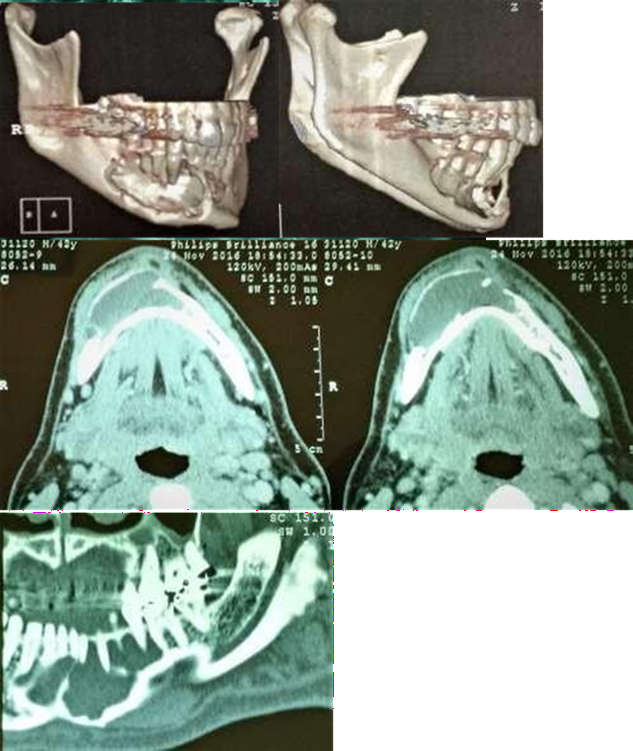

Figure 3. Initial CT scan showing bony lesion

Upon clinical examination, an expansive

mandibular lesion was noted, the buccal bone plate presented slight crackling

and no teeth mobility was observed (Figure

1). Radiographic and tomographic examination (Figure 2 & Figure 3)

revealed an ill-defined multilocular radiolucency, with “honeycomb” aspect,

adjacent to the roots of the lower right canine and premolars, without

mandibular base involvement. Pulp vitality test was applied using endofrost

(cold) and gutta percha (heat), revealing vital canine and non-vital premolars.